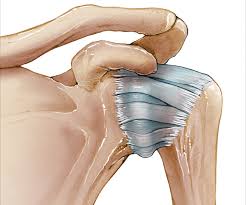

오십견은 유착성 관절낭염이나 동결견(frozen shoulder)라는 다른 이름으로 명명되어 지는데 임상적으로 볼 때 운동제한을 동반한 어깨 통증과 야간통증이 있을 때 의심하게 되는 질병으로 운동범위 검사와 어깨 MRI를 통해서 진단한다고 한다.

일반적으로 외상이나 지속적인 고정 후에 발병하지만 회전근개의 질환이나 석회성 건염 같은 질환, 또는 중풍, 심근경색, 당뇨 등에 의해 속발성으로 나타나기도 한다고 한다.

질병의 양상이 4단계의 경과를 밟게 되는데 1단계는 염증기(0-3개월)로 움직일 때 통증과 약간의 경직이 있으며, 2단계는 동결진행기(3-9개월)로 통증과 경직이 더 심해지며, 3단계는 동결기(9-15개월)로 통증은 감소하지만 경직이 뚜렷하게 심해지며 마지막 단계는 해동기(1-24개월)로 점차적으로 경직이 풀리고 통증이 완화되는 시기라고 한다.